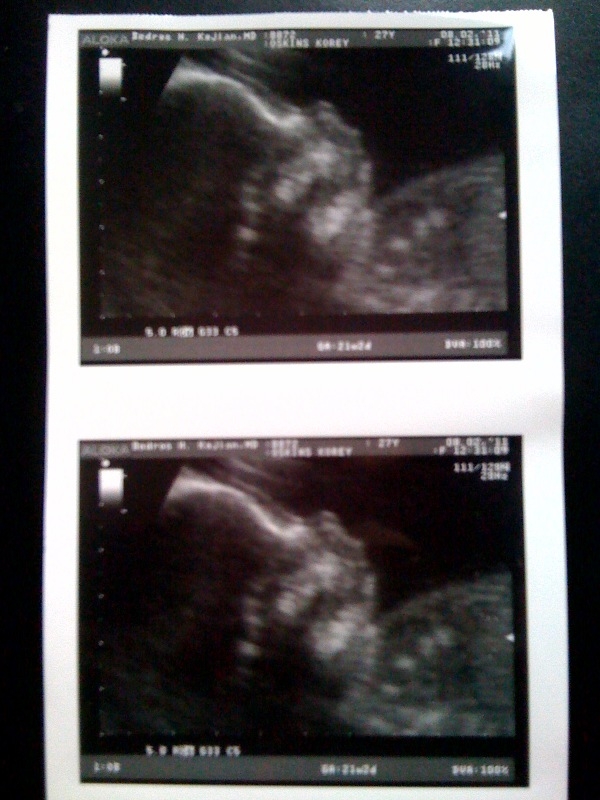

Want to see a glimpse of our baby’s face? Well so do I! But this is what we get for now…